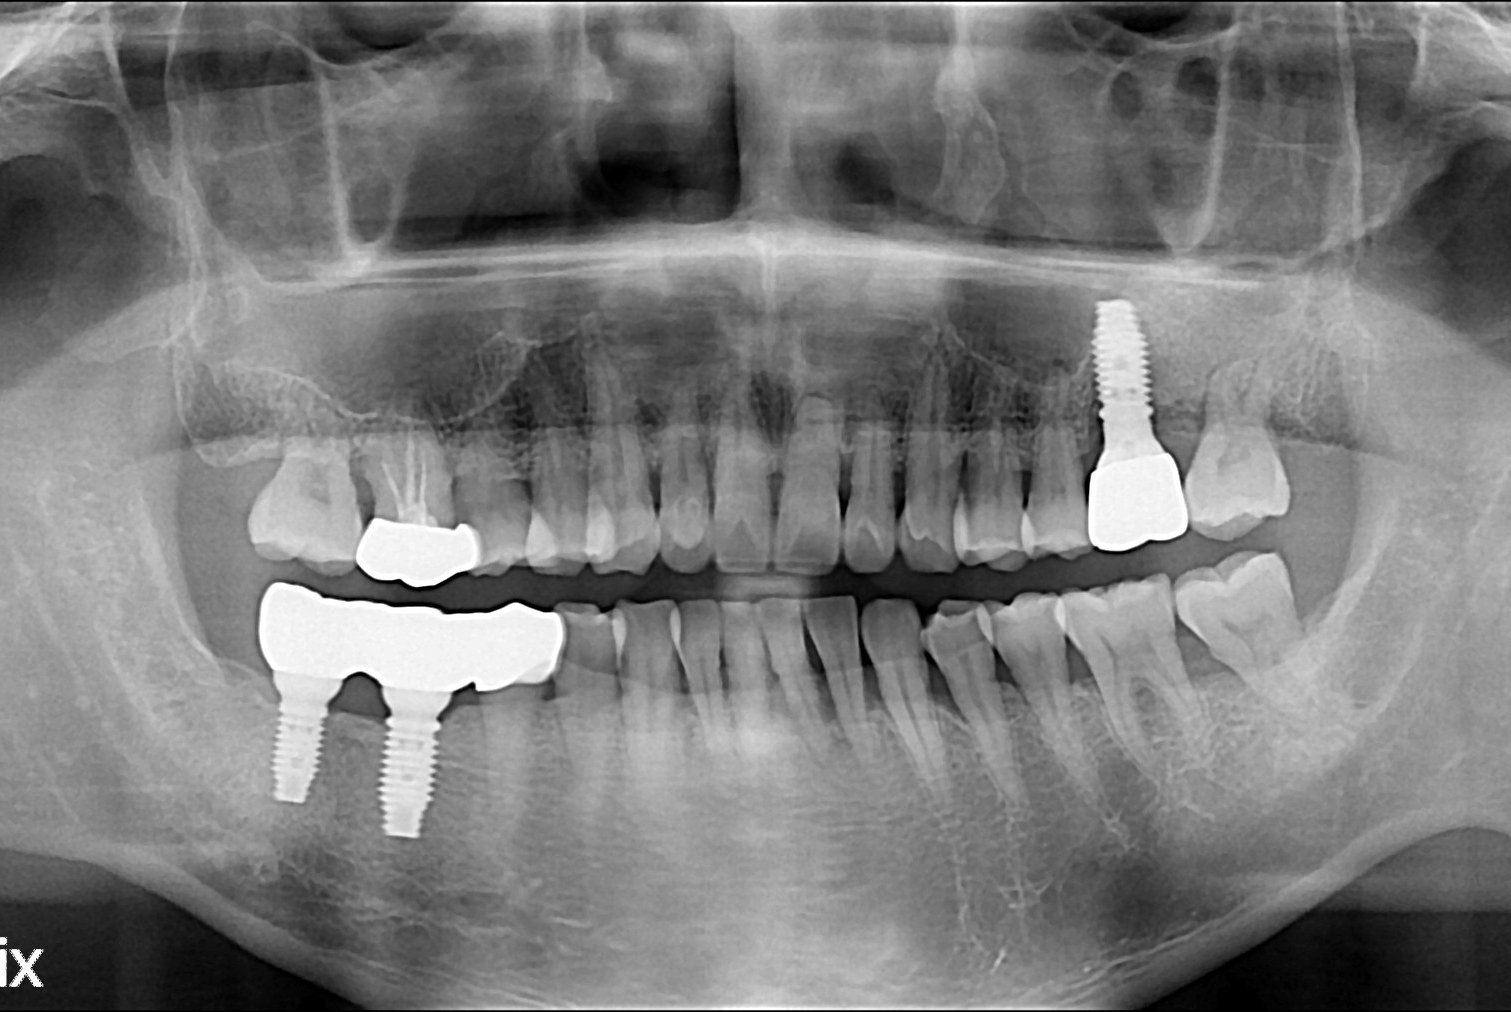

치료후 : 2019-12-18

세종치과는 많은 환자와 다양한 케이스를 바탕으로 항상 편안한 임플란트 수술을 제공하고자 노력하고,

오래동안 튼튼히 쓸 수 있는 임플란트 수술을 가장 큰 목표로 삼고 있습니다